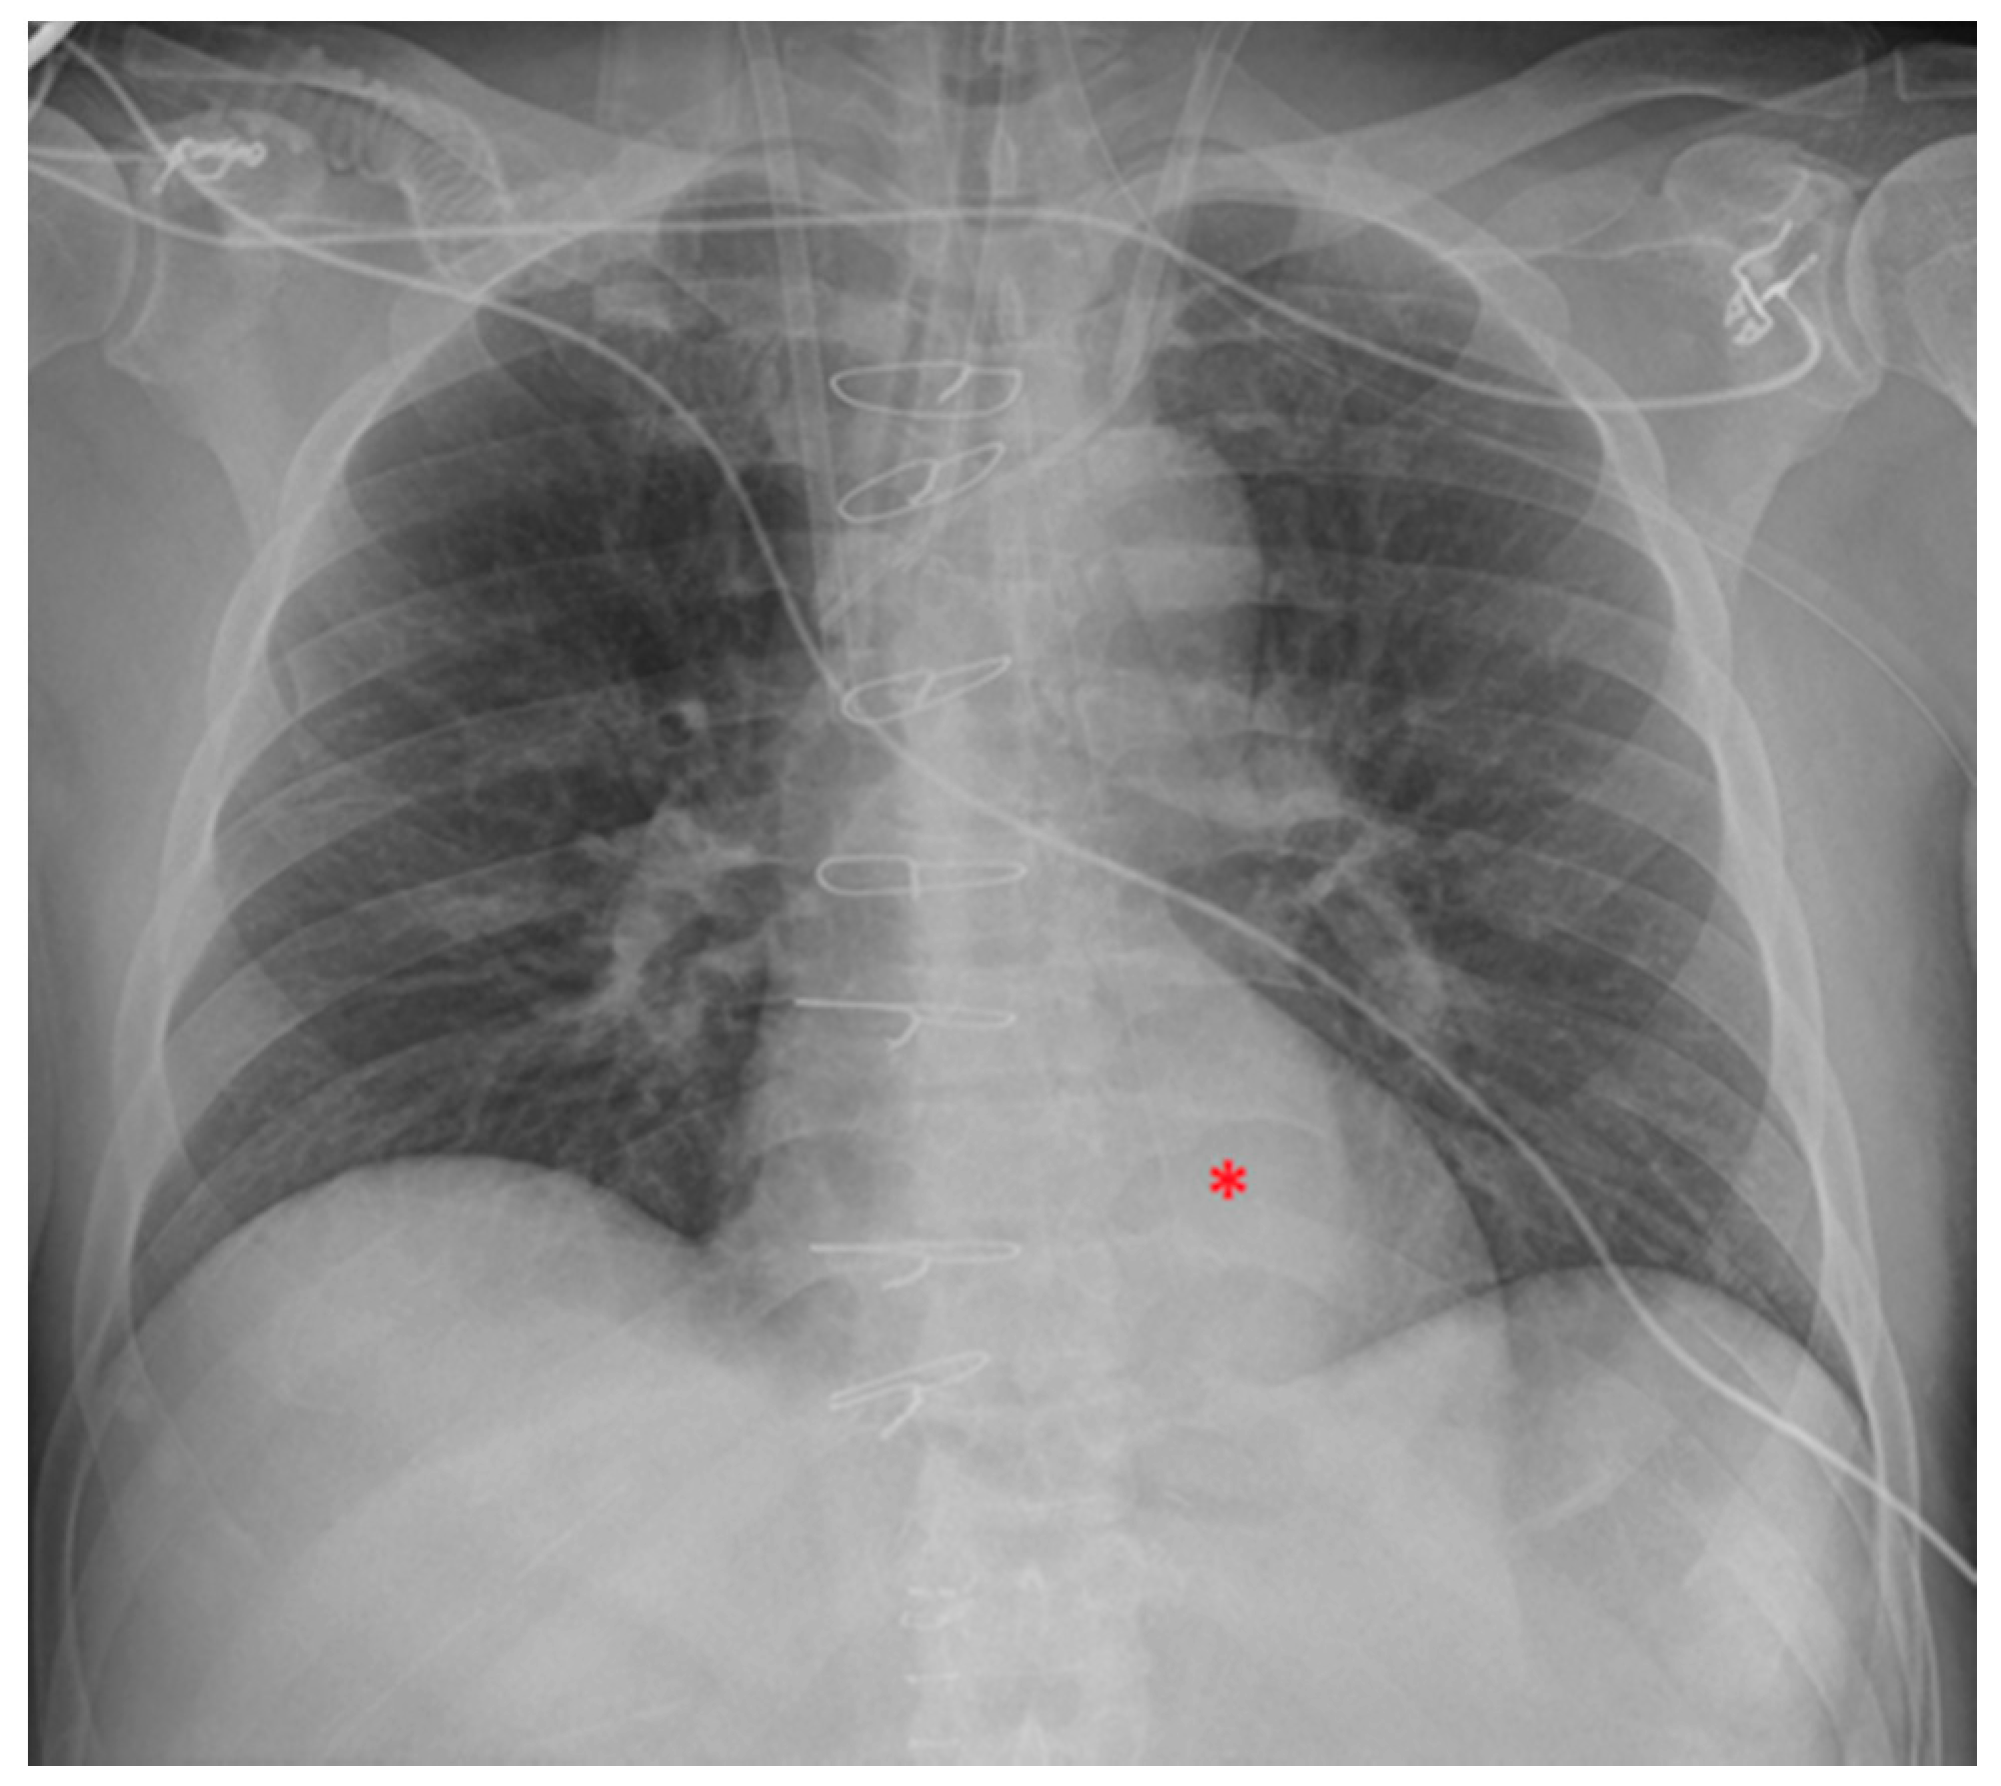

Image of NG tube positioned too proximally, its tip reaching the distal oesophagus and therefore projecting against the heart (red asterisk). In the same patient, the ETT has been pushed too low, with its tip proximal to the carina. The picture also shows two left jugular CVCs and a right jugular CVC.